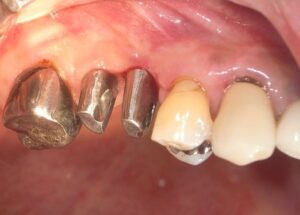

本日無事にアバットと仮歯が入りました

この仮歯で食事をしてみて歯周組織との調和を観察します。